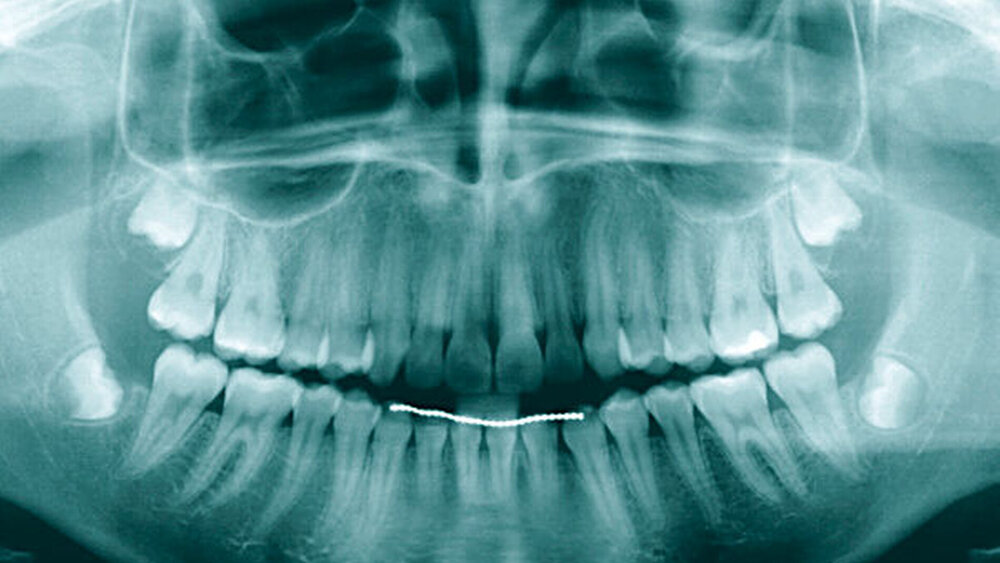

Der extraorale Befund war bis auf ein Hämatom im Kinnbereich unauffällig. Eine Kiefergelenksfraktur wurde bereits am Vortag im unmittelbar nach dem Unfall aufgesuchten Klinikum Ludwigshafen ausgeschlossen. Intraoral zeigte sich ein vollständiges, kariesfreies Gebiss mit Z. n. abgeschlossener kieferorthopädischer Therapie. Die Zähne 14 und 15 hatten einen Lockerungsgrad II sowie eine alio loco angebrachte flexible SÄT-Drahtschienung. An den Zähnen 16, 26, 45 und 46 wies die Patientin z. T. ausgedehnte Schmelz-Dentin-Abscherungen auf. Nach Entfernung der Schienung 14 Tage später zeigten sich die komplizierten Kronen-Wurzel-Frakturen an 14 und 15.

Auch bei scheinbar nicht optimalen Grundvoraussetzungen – wie einem zu erwartenden nicht ganz idealen Kronen-Wurzel-Verhältnis (1:1) – scheint die kieferothopädische Extrusion als Behandlungsoption nicht direkt ausgeschlossen werden zu müssen. Auf dem im Fall gezeigten OPG (Abbildung 9) stellen sich die Zahnwurzeln von 14 und 15 im kontralateralen Vergleich deutlich kürzer dar als die der Zähne 24 und 25. Die elektronische Messlänge bei der Revision der endodontischen Behandlung von Zahn 15 vor Eingliederung des Langzeitprovisoriums betrug lediglich 12 mm. Dennoch wiesen die Zähne 14 und 15 nach der Retentionsphase keine Lockerungsgrade auf, sodass die Autoren in der vermeintlich geringen Wurzellänge keine unbedingte Kontraindikation für das Ziel der Zahnerhaltung sehen. Auch wenn in diesem Fall die unterschiedliche Zahnlänge der Prämolaren im kontralateralen Vergleich klar mit der Extrusion der Zähne 14 und 15 zu erklären ist, stellen kieferorthopädische Bewegungen auch eine mögliche Ursache für die Verkürzung von Zahnwurzeln durch Resorptionen dar.